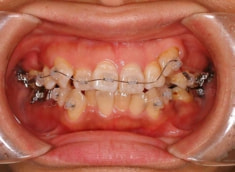

治療開始時

治療開始から約1年2ヶ月後